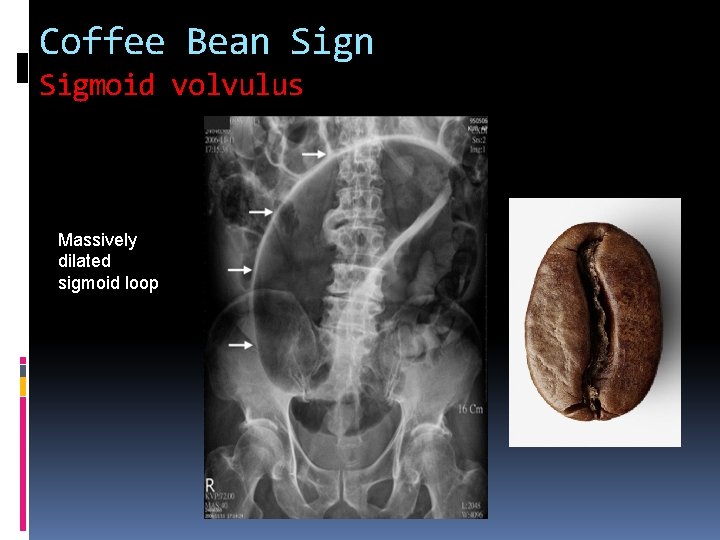

Coffee Bean Sigmoid volvulus Massively dilated sigmoid loop